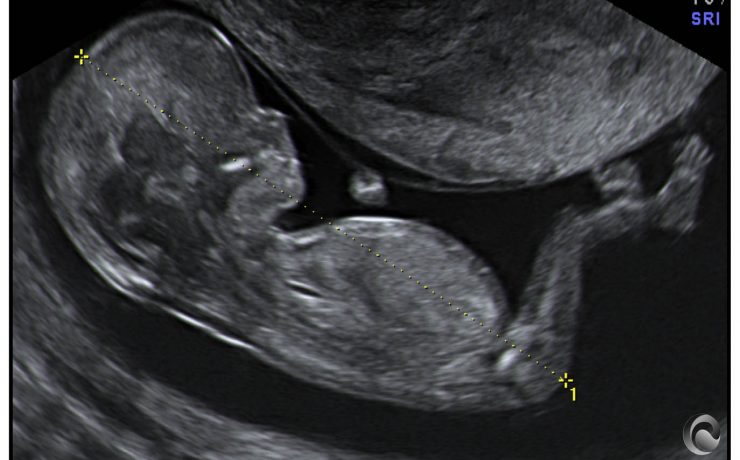

La muerte u óbito fetal se define como la ausencia de latido cardíaco, pulsación de cordón, respiración espontánea y movimientos del feto, antes de la separación completa del cuerpo de la madre. Aunque en algunos países se considera desde que el feto pesa 350 g y en otros se utiliza